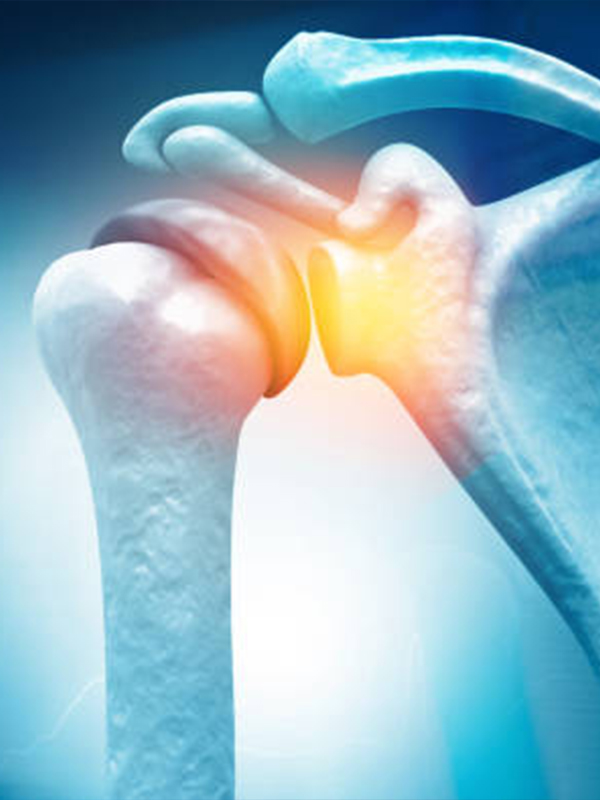

DR.S.VIGNESH MBBS, M.S (Ortho) joint replacement surgeon specializing in the treatment of Sports injuries, arthritis and other degenerative joint conditions of the Shoulder, hip and knee. Through his extensive training and experience, he has developed an expertise in joint replacement surgeries, such as total knee replacement, Hip replacement, Shoulder replacement, Arthroscopy of shoulder and knee joints, and minimally invasive fracture fixation procedures.